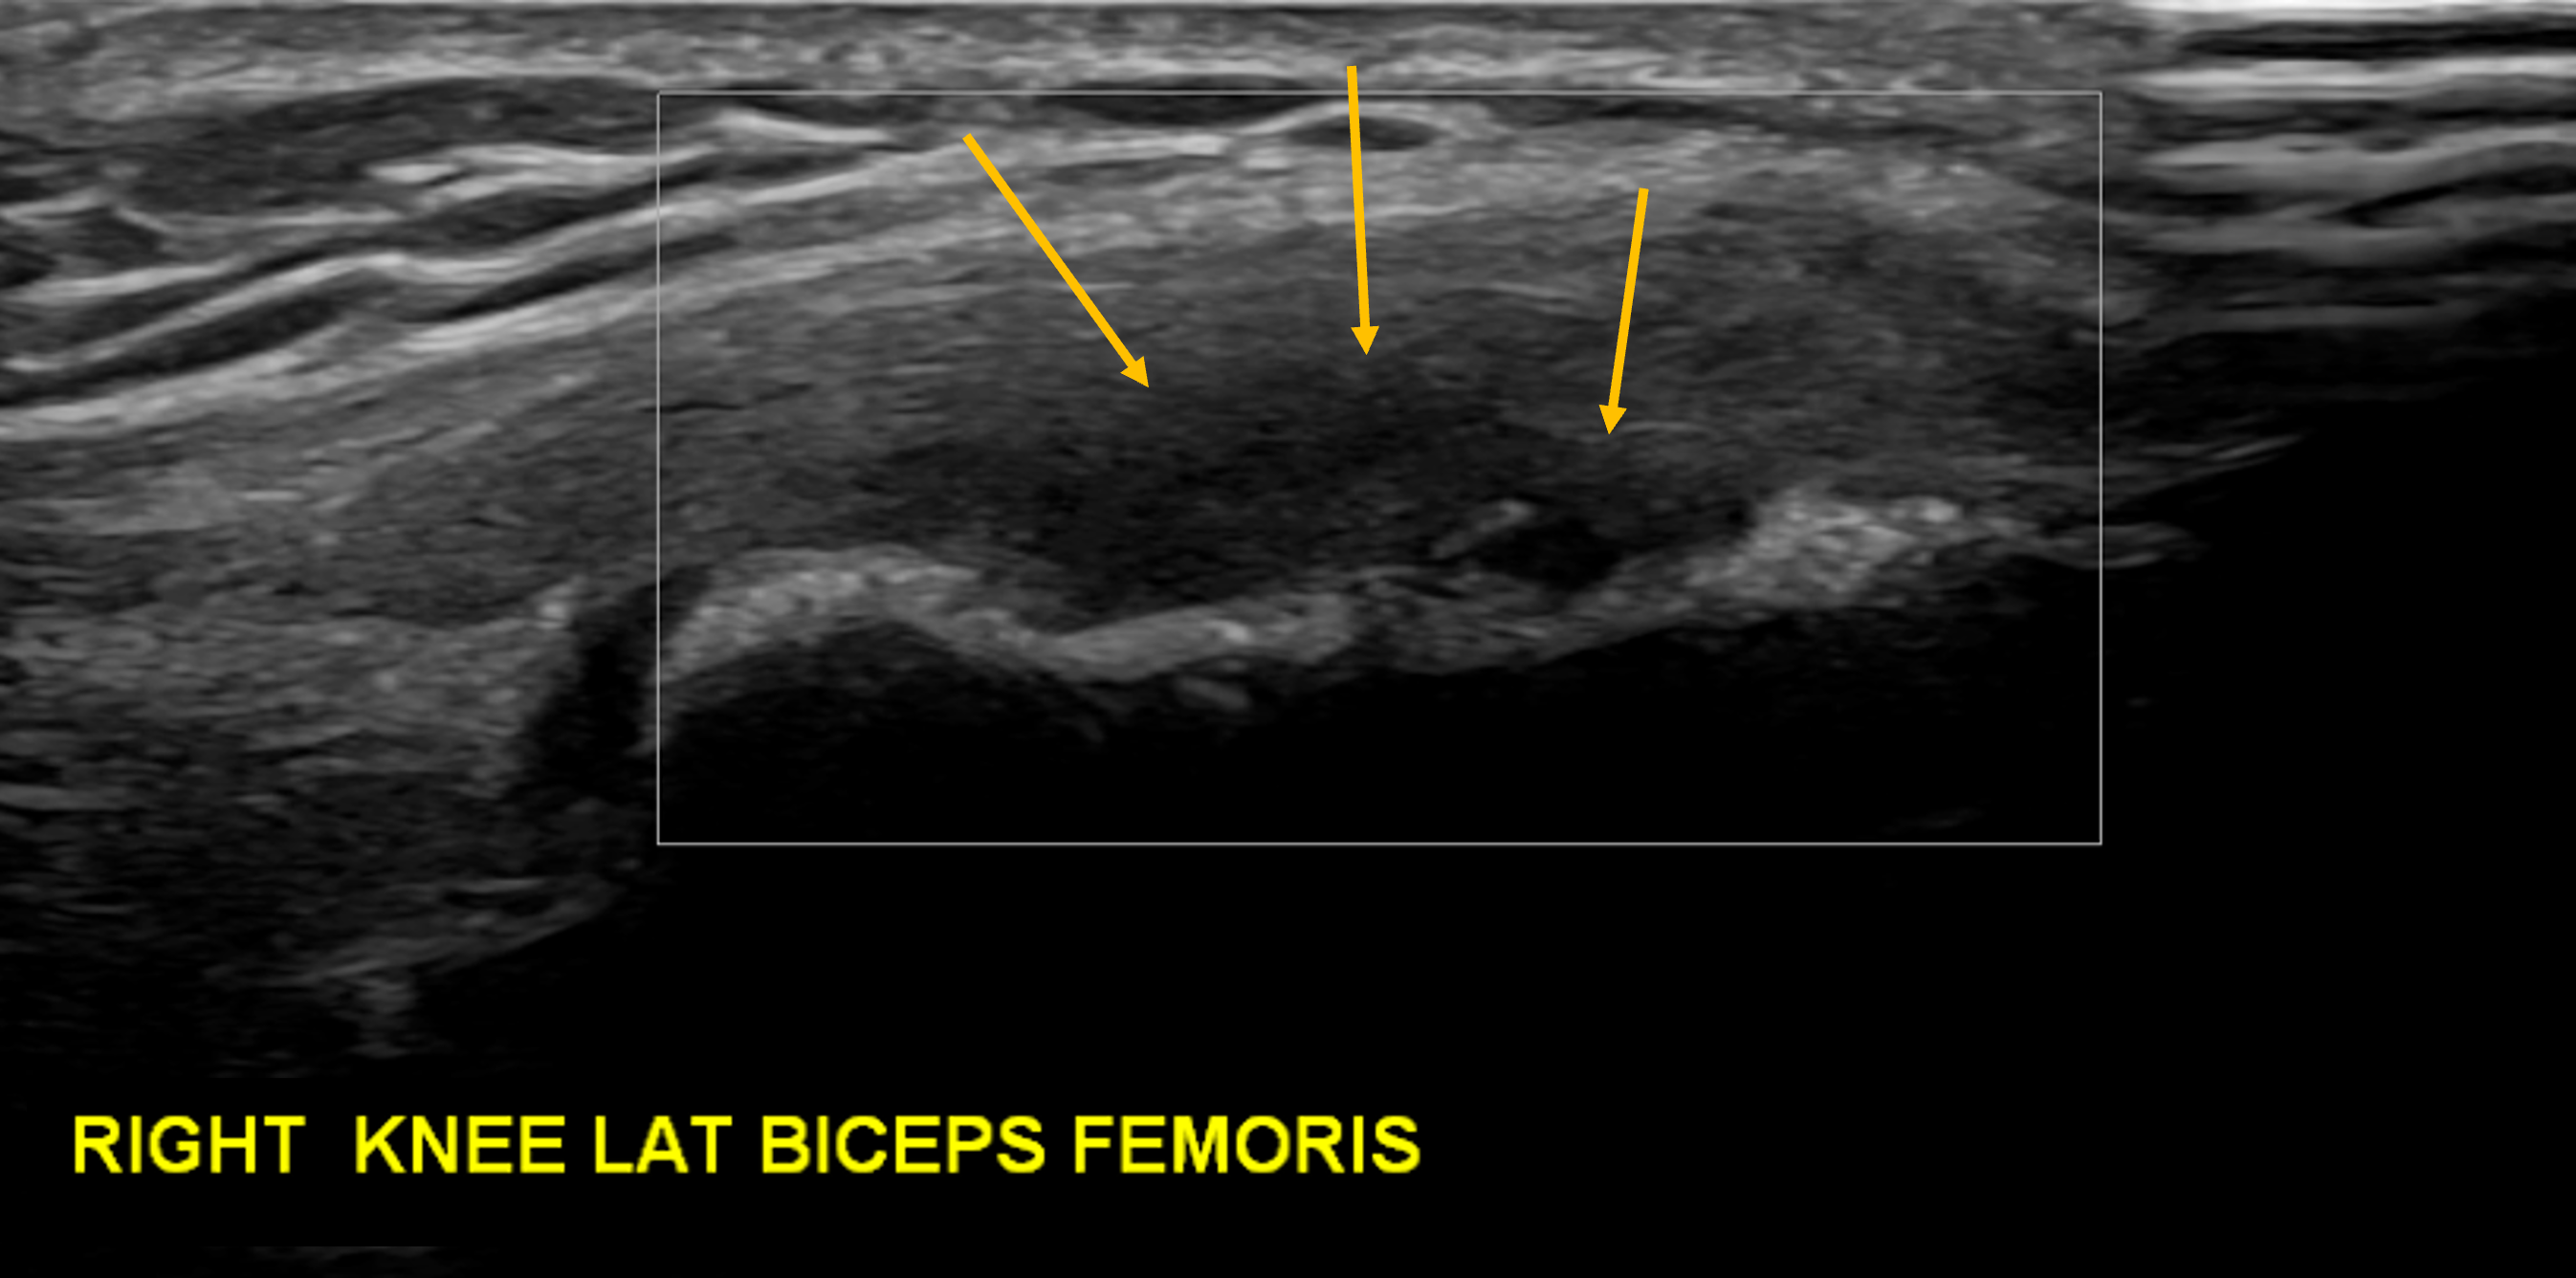

This is an overuse condition triggered by sports where there is repetitive acceleration and deceleration, such as running and football. This patient is a triathlete. The image demonstrates a loss of the normal fibrillar pattern at the BF insertion (arrows) in keeping with tendinopathy. There was no neo-vascularity present.